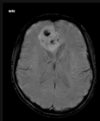

4

Q

A

Esclerose mesial temporal

Observe a perda de volume, que indica atrofia e causa aumento secundário do corno temporal do ventrículo lateral.

O sinal alto no hipocampo reflete a gliose.